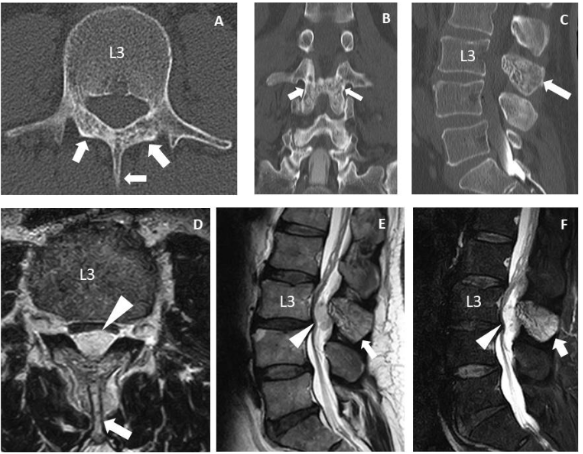

A 47-year-old male presented with a 6-month history of worsening low back and lower limb pain. He had no family history or previous history of malignant tumor or spinal trauma. Previous examination at another hospital found urinary incontinence and sensory disturbance from the lower limbs to anus associated with the pain. Computed tomography showed intraosseous abnormal signals in the bilateral laminae and spinal process at the L3 level (Figure 1A-1C). Magnetic resonance imaging (MRI) also revealed an epidural lesion with a maximum size of 23 mm at the same level (Figure 1D-1F). On admission to our hospital one month later, he showed similar urinary incontinence without motor deficits, but sensory disturbance had extended to the posterior surface of the thighs with pain. MRI demonstrated no changes in the intraosseous lesion but rapid growth of the epidural lesion with a maximum size of 74 mm extending over the L2-L4 levels within only one month (Figure 2A-2C). The epidural lesion seemed to be radiologically isolated from the intraosseous lesion. T1-weighted MRI showed the epidural lesion as mixed-intensity areas inside capsular barriers. T2-weighted imaging and short T1 inversion recovery imaging also showed the lesion as hyperintense (Figure 2A-2C, 2E). The lesion was almost homogeneously enhanced (Figure 2D). Preoperative diagnoses were NST or metastatic spinal tumor of unknown origin.

Figure 1 Images obtained at the previous hospital. Computed tomography (CT) scan (A) and CT myelograms (B, C) showed abnormal translucent signals (white arrows) at the L3 spinal processes and laminae. Magnetic resonance images (D–F) showed an epidural mass lesion (white arrowheads) at the same level. This well-demarcated lesion seemed to be isolated from the intraosseous lesions (white arrows).